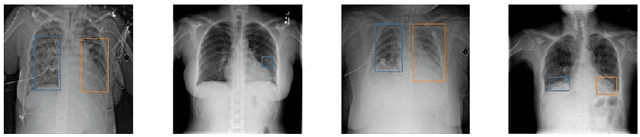

Abstract:Deep neural networks (DNNs) have been expanded into medical fields and triggered the revolution of some medical applications by extracting complex features and achieving high accuracy and performance, etc. On the contrast, the large-scale network brings high requirements of both memory storage and computation resource, especially for portable medical devices and other embedded systems. In this work, we first train a DNN for pneumonia detection using the dataset provided by RSNA Pneumonia Detection Challenge. To overcome hardware limitation for implementing large-scale networks, we develop a systematic structured weight pruning method with filter sparsity, column sparsity and combined sparsity. Experiments show that we can achieve up to 36x compression ratio compared to the original model with 106 layers, while maintaining no accuracy degradation. We evaluate the proposed methods on an embedded low-power device, Jetson TX2, and achieve low power usage and high energy efficiency.